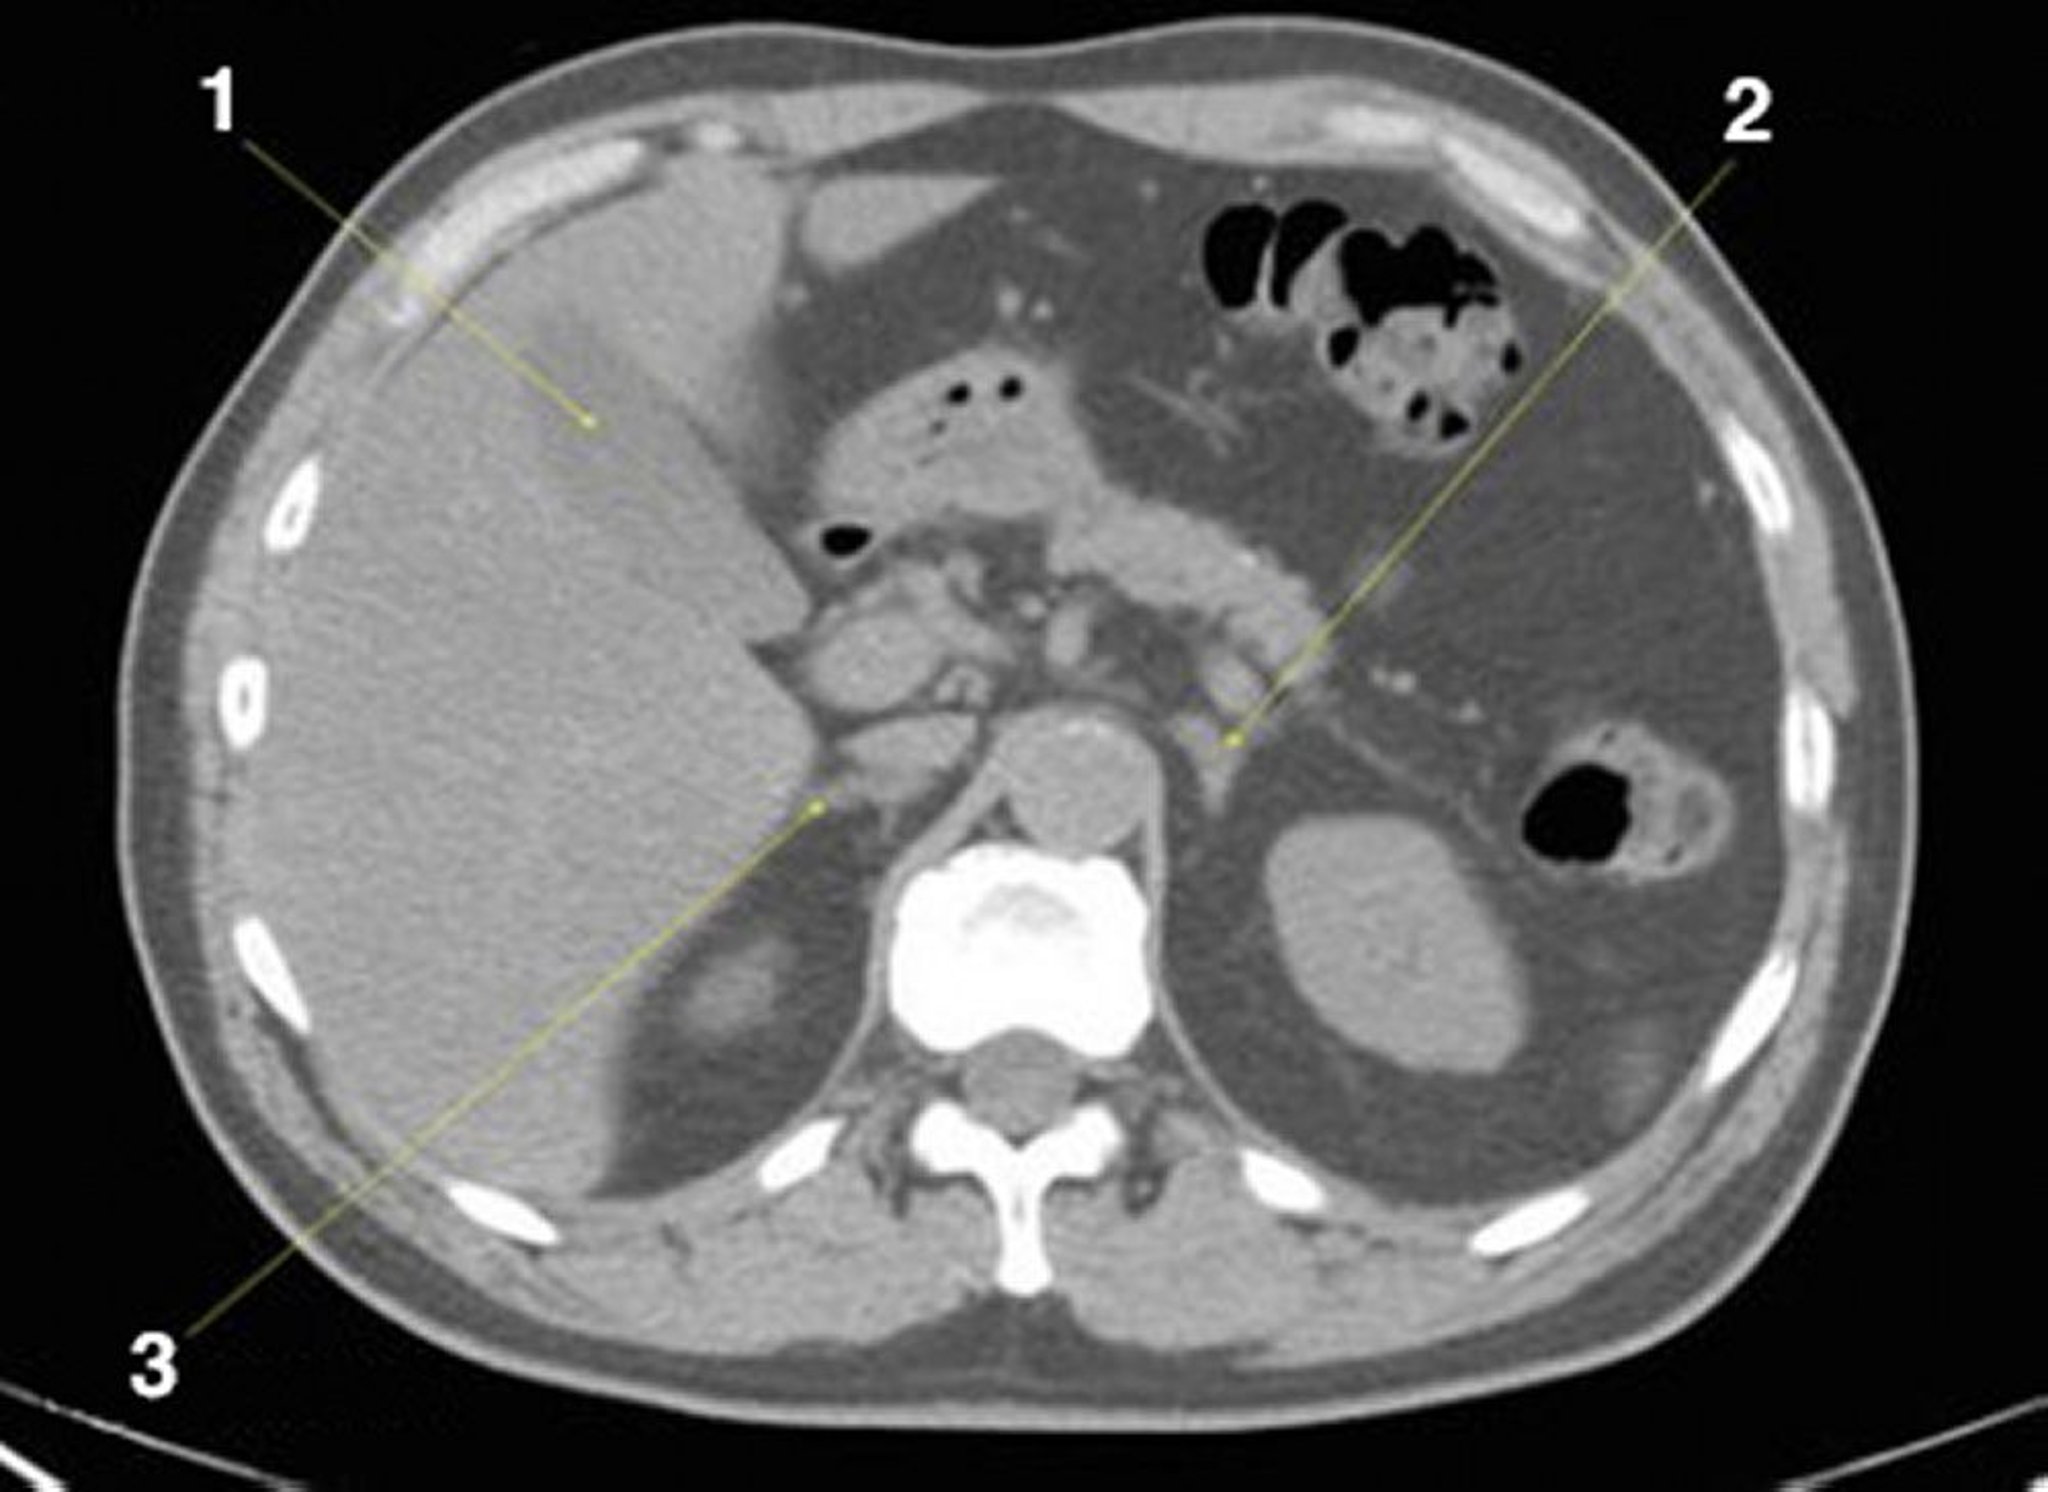

Phim chụp CT vùng bụng và vùng chậu không thuốc cản quang cho thấy giải phẫu bình thường (lát cắt 8)

1 = túi mật; 2 = tuyến thượng thận trái; 3 = tuyến thượng thận phải.